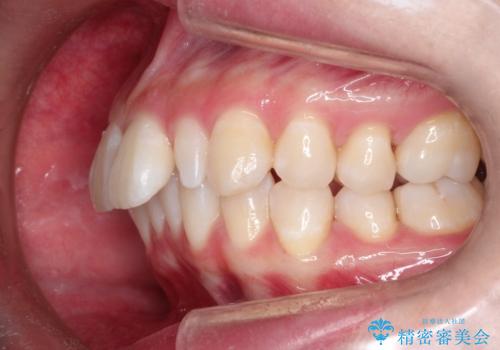

- 出っ歯と全体をきれいにしたいとのことで来院されました。

上顎の歯が全体的に前方に位置しているのと、前から2番目の歯が通常よりも小さい矮小歯という状態でした。

出っ歯をなおすために上顎の前から4番目の歯を抜歯して、引っ込めるのと、前から2番目の歯に通常の大きさのオールセラミックを装着して整った歯並びにすることにしました。